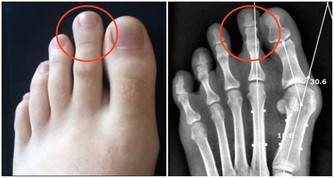

10.易發生肌肉痙攣: 久坐使血流不暢,肌肉僵硬、痠痛、萎縮,使肌肉失去力量和彈性而發生痙攣。 11.會引起腰背疼痛: 久坐使得整個軀體重量全部壓在腰骶部,使腰背肌長期處於緊張狀態。